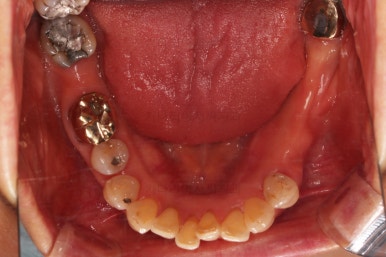

초진 시 입안의 모습입니다.

일반적인 교정을 하기에는 적합한 모습은 아니었어요.

치아는 군데군데 없고 임플란트도 있고 브릿지로 연결된 치아도 있으며 전반적인 잇몸 상태도 좋지 못했어요.

앞니가 벌어져 있고 뻗쳐 있으며 잇몸에서 쏙 빠져나와 있는 듯한 느낌이었어요.